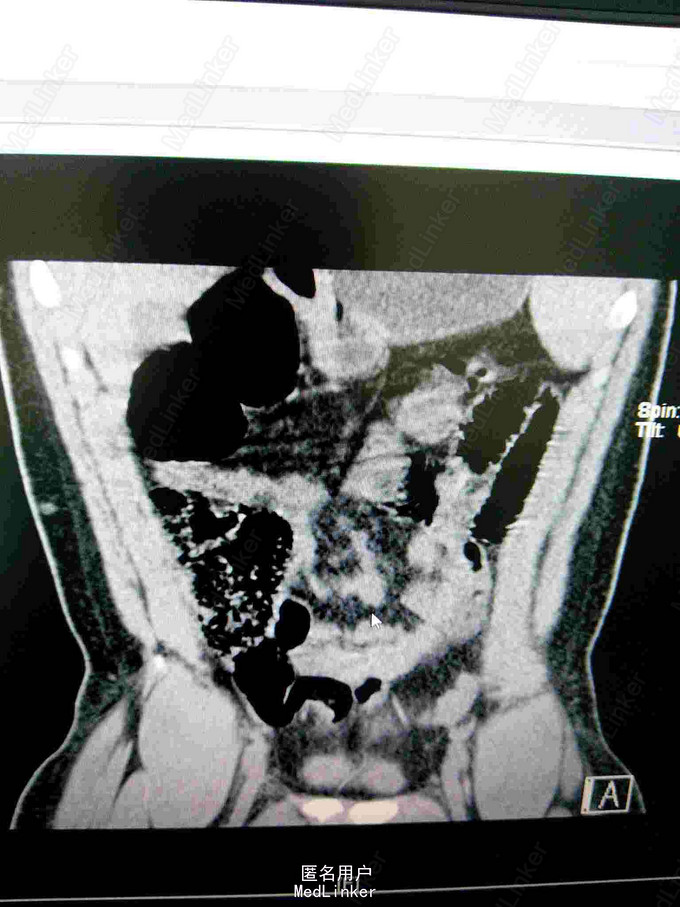

23岁男性患者,非洲加纳人,因"腹部疼痛半天"来院,现病史:患者半天前无明显诱因出现腹部疼痛,以下腹部持续性疼痛为主,阵发性加重,无发热,无呕吐,无腹胀腹泻,无尿频尿急尿痛等不适。患者有镰状细胞性贫血病史多年。

查体:神清,生命征平稳,急性痛苦面容,大汗淋淋,腹平,下腹部压痛明显,可疑反跳痛,无明显固定压痛点,上腹部轻度压痛,肝脾肋下未及,墨非氏征阴性,未及包块,双肾区无压痛扣击痛,输尿管行程无压痛,移动性 胞 浊音阴性,肠鸣音活跃。查血常规白细正常,中性正常,HGB95g/l,HCT26.7%,MC63.7fl,MCH22.7pg,MCHC356g/l,红细胞分布宽度差异23.7%,红细胞分布宽度标准53fl.淀粉酶正常。

镰状细胞性贫血并发肠绞痛。治疗:予补液,扩容,解痉止痛等对症处理。